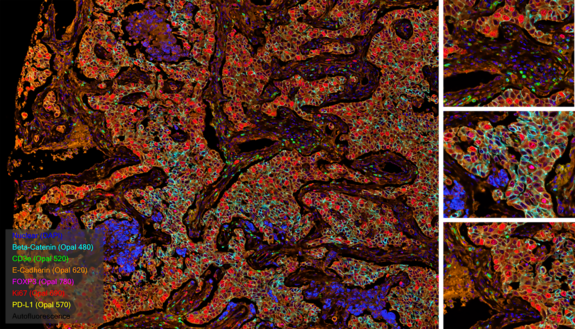

Multiplex immunofluorescence image showing tissue section with multicolor staining for different cell markers

Multiplex immunofluorescence image showing tumor tissue stained for Beta-Catenin, CD8α, E-Cadherin, FOXP3, Ki67, and PD-L1

Invasive ductal carcinoma Grade I stained with 6-plex mIF.

At Fortis, we use TSA on slides produced for the Akoya PhenoImager™ HT using Opal™ reagents to generate up to 6-plex images.